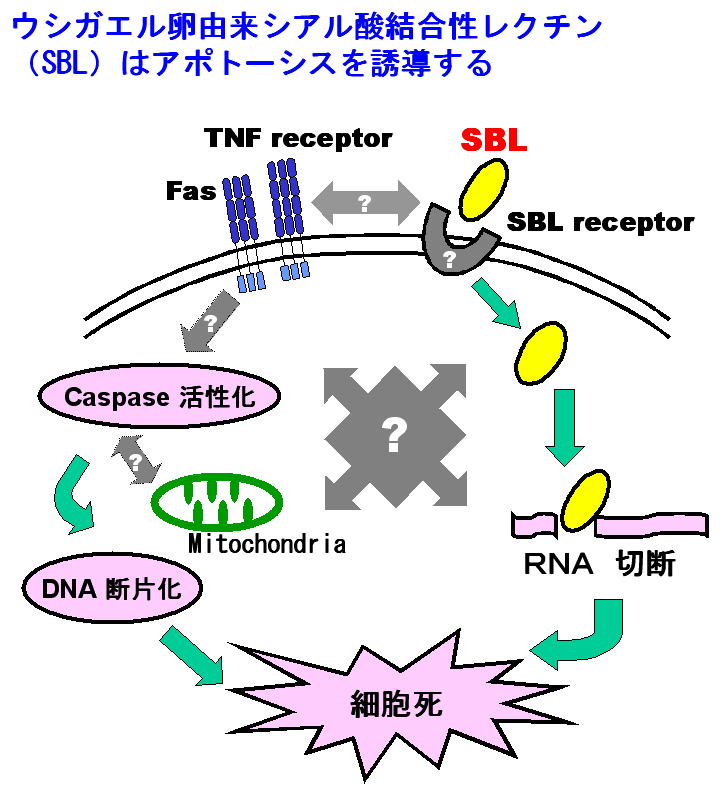

ウシガエルなどのアカガエル属のカエル卵には,シアル酸結合性レクチン(SBL)が含まれている.SBLとリボヌクレアーゼ(RNase)のアミノ酸配列には相同性が認められ,SBLにはRNase活性が観察されている.また,SBLには抗腫瘍作用が認められており,この作用はSBLの「細胞表面のシアル酸を含む糖鎖を認識して結合する」レクチン活性と「細胞の生存に必要なRNAを分解する」RNase活性が協働することにより発揮されると考えられている.しかもこの作用は,腫瘍細胞にアポトーシスと呼ばれる細胞死を引き起こす. SBLによるアポトーシス誘導機構には,「SBL受容体に対するSBLの結合」および「SBLのRNase活性によるRNAの分解およびSBLを発信源とするアポトーシスシグナルの伝達」が重要な課題である.白血病細胞や悪性中皮腫細胞などの腫瘍細胞での,SBLレセプターの解明およびアポトーシスシグナル伝達のメカニズムに関する研究が進行中である.

現在,想定されている機構を下記の図に示す.